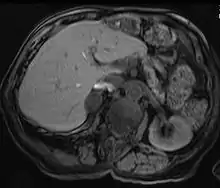

الكبد

الأورام الكبدية هي أورام نادرة حميدة، وقد تظهر مع تضخم الكبد أو مع أعراض أخرى.